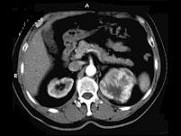

- 多项选择题男,65岁, 左侧腰背部胀痛伴无痛性全程血尿3月余,CT平扫及增强检查如图所示, 下列说法正确的是 ( )

A、平扫时见左肾上极有一软组织肿块影,其边界较清楚

B、增强扫描肾皮质期可见肿块明显强化,其内亦有无强化区

C、增强扫描肾实质期可见肿块强化迅速下降,但密度比平扫时仍要高

D、考虑为左侧肾癌

E、考虑为左侧肾错构瘤